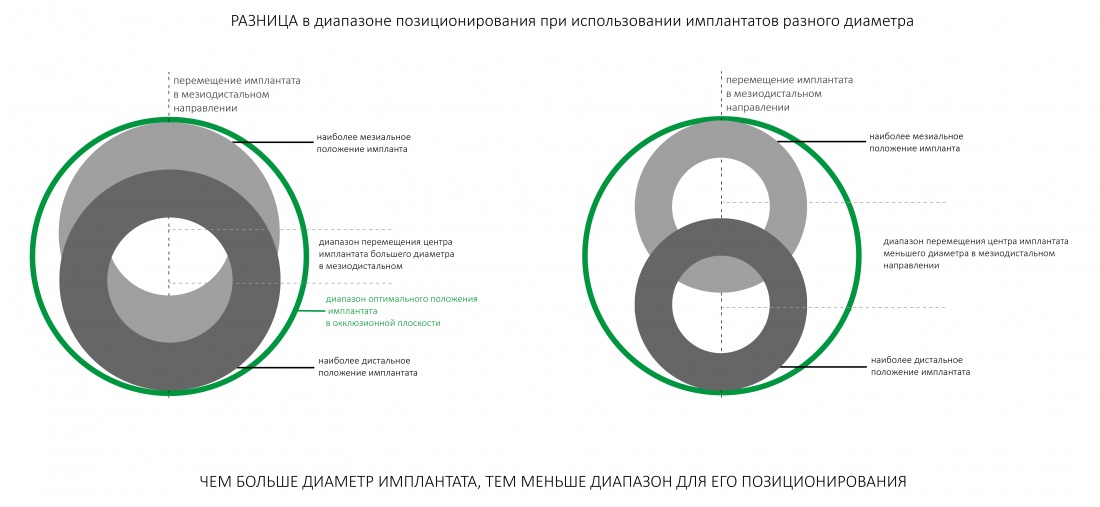

Чтобы ответить на этот вопрос, обратимся к геометрии:

Большой зеленый круг — это область, приемлемого положения имплантата. Поместив в неё два разных по диаметру импланта, мы заметим, что диапазон позиционирования импланта большего диаметра существенно меньше, чем импланта меньшего диаметра — это хорошо видно по рисунку выше. То есть, имплантат большого диаметра хорош до определенного предела, у импланта меньшего диаметра больше вариантов для правильного позиционирования. И это следует учитывать, особенно в случаях немедленной имплантации:

Простой пример выше — лунка премоляра и объемы костной ткани позволяют нам, как видите, использовать три разных диаметра имплантата, от 3,8 до 5,5 мм. Однако, возможностей для правильного позиционирования больше у имплантата диаметром 3,8 мм, поскольку по бокам от него еще остается «свободное пространство», чего не скажешь об имплантате диаметром 5,5 мм.